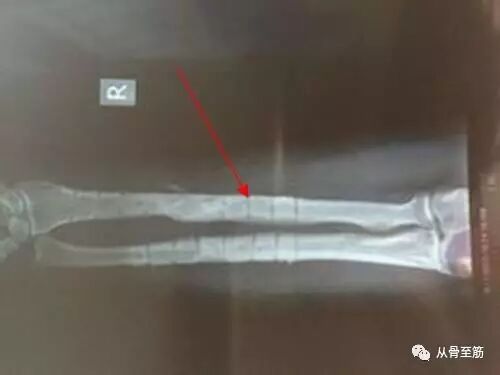

? ?原因之一:在医学上有个术语,叫“应力遮挡”,就是在骨折断端正常的应力被钢板或髓内钉给挡住了,一部分的力量是通过内固定物传导过去了。而骨折的愈合及愈合后的改造塑型需要正常的应力刺激,由于内固定物的存在,骨折断端应力刺激相对减少,因此愈合的强度与正常骨质仍有区别。一旦去除内固定物,断端失去了保护,如果过早负重,则有可能再骨折。